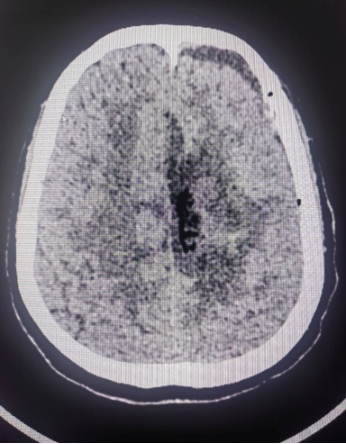

患者系中年女性,因出现偏侧肢体活动不灵和头痛症状,经检查发现颅内大脑镰旁长有一直径7cm的巨大肿瘤。肿瘤位于大脑的运动功能区,血供丰富,这一区域的手术风险极大。在决定手术治疗之前,神经外科医生与患者家属进行了充分的沟通,详细解释了手术的必要性、可能的风险和并发症,包括出血、感染、血管和神经损伤以及脑功能障碍等。家属在充分了解情况后,同意进行手术。面对这一复杂病例,我院迅速组织了由神经外科、麻醉科、心内科、输血科等多个科室的专家团队进行会诊,共同制定了先介入栓塞,再手术切除的治疗方案。

神经外科血管介入组曲友直副教授、崔刚副教授和高攀主治医师对肿瘤进行了瘤栓塞治疗,有效减少了肿瘤的血供,为后续的手术切除降低了风险。栓塞治疗后,神经外科王睿智副主任、高李贵副教授和董全主治医师在麻醉科、心内科、输血科等科室的全力配合下,凭借精湛的医术和丰富的临床经验,成功为患者切除了病变。手术过程中,麻醉科吕建瑞主任团队全程监控患者的生命体征,确保麻醉安全;心内科团队随时准备应对可能出现的心脏问题;输血科团队则确保充足的血液供应,以备不时之需。多学科的通力合作,为手术的成功提供了坚实的保障。